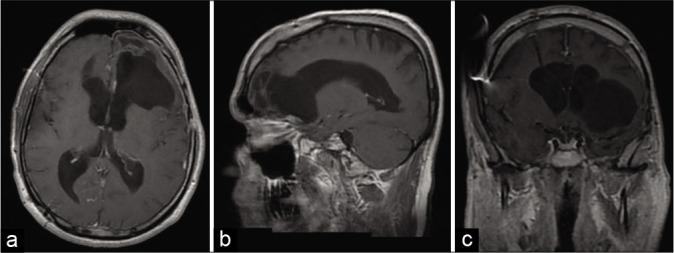

一名39岁男性,因交通性脑积水置入了脑室腹腔分流管,因有1个月的步态障碍、姿势不稳、言语障碍及偶尔失禁的病史入住我们的神经外科病房。计算机断层扫描和磁共振成像显示左额颞区有一个混合密度肿瘤,伴有大脑镰前部移位及瘤周水肿。患者接受了手术;通过左翼点入路对病变进行了显微手术切除。组织病理学和免疫组织化学检查显示为神经元谱系的单形性圆形细胞,Ki-67阳性核百分比<5%,且无有丝分裂或坏死区域的证据。根据影像学特征,这种表现符合EVN的诊断。患者恢复良好,仍在随访中。